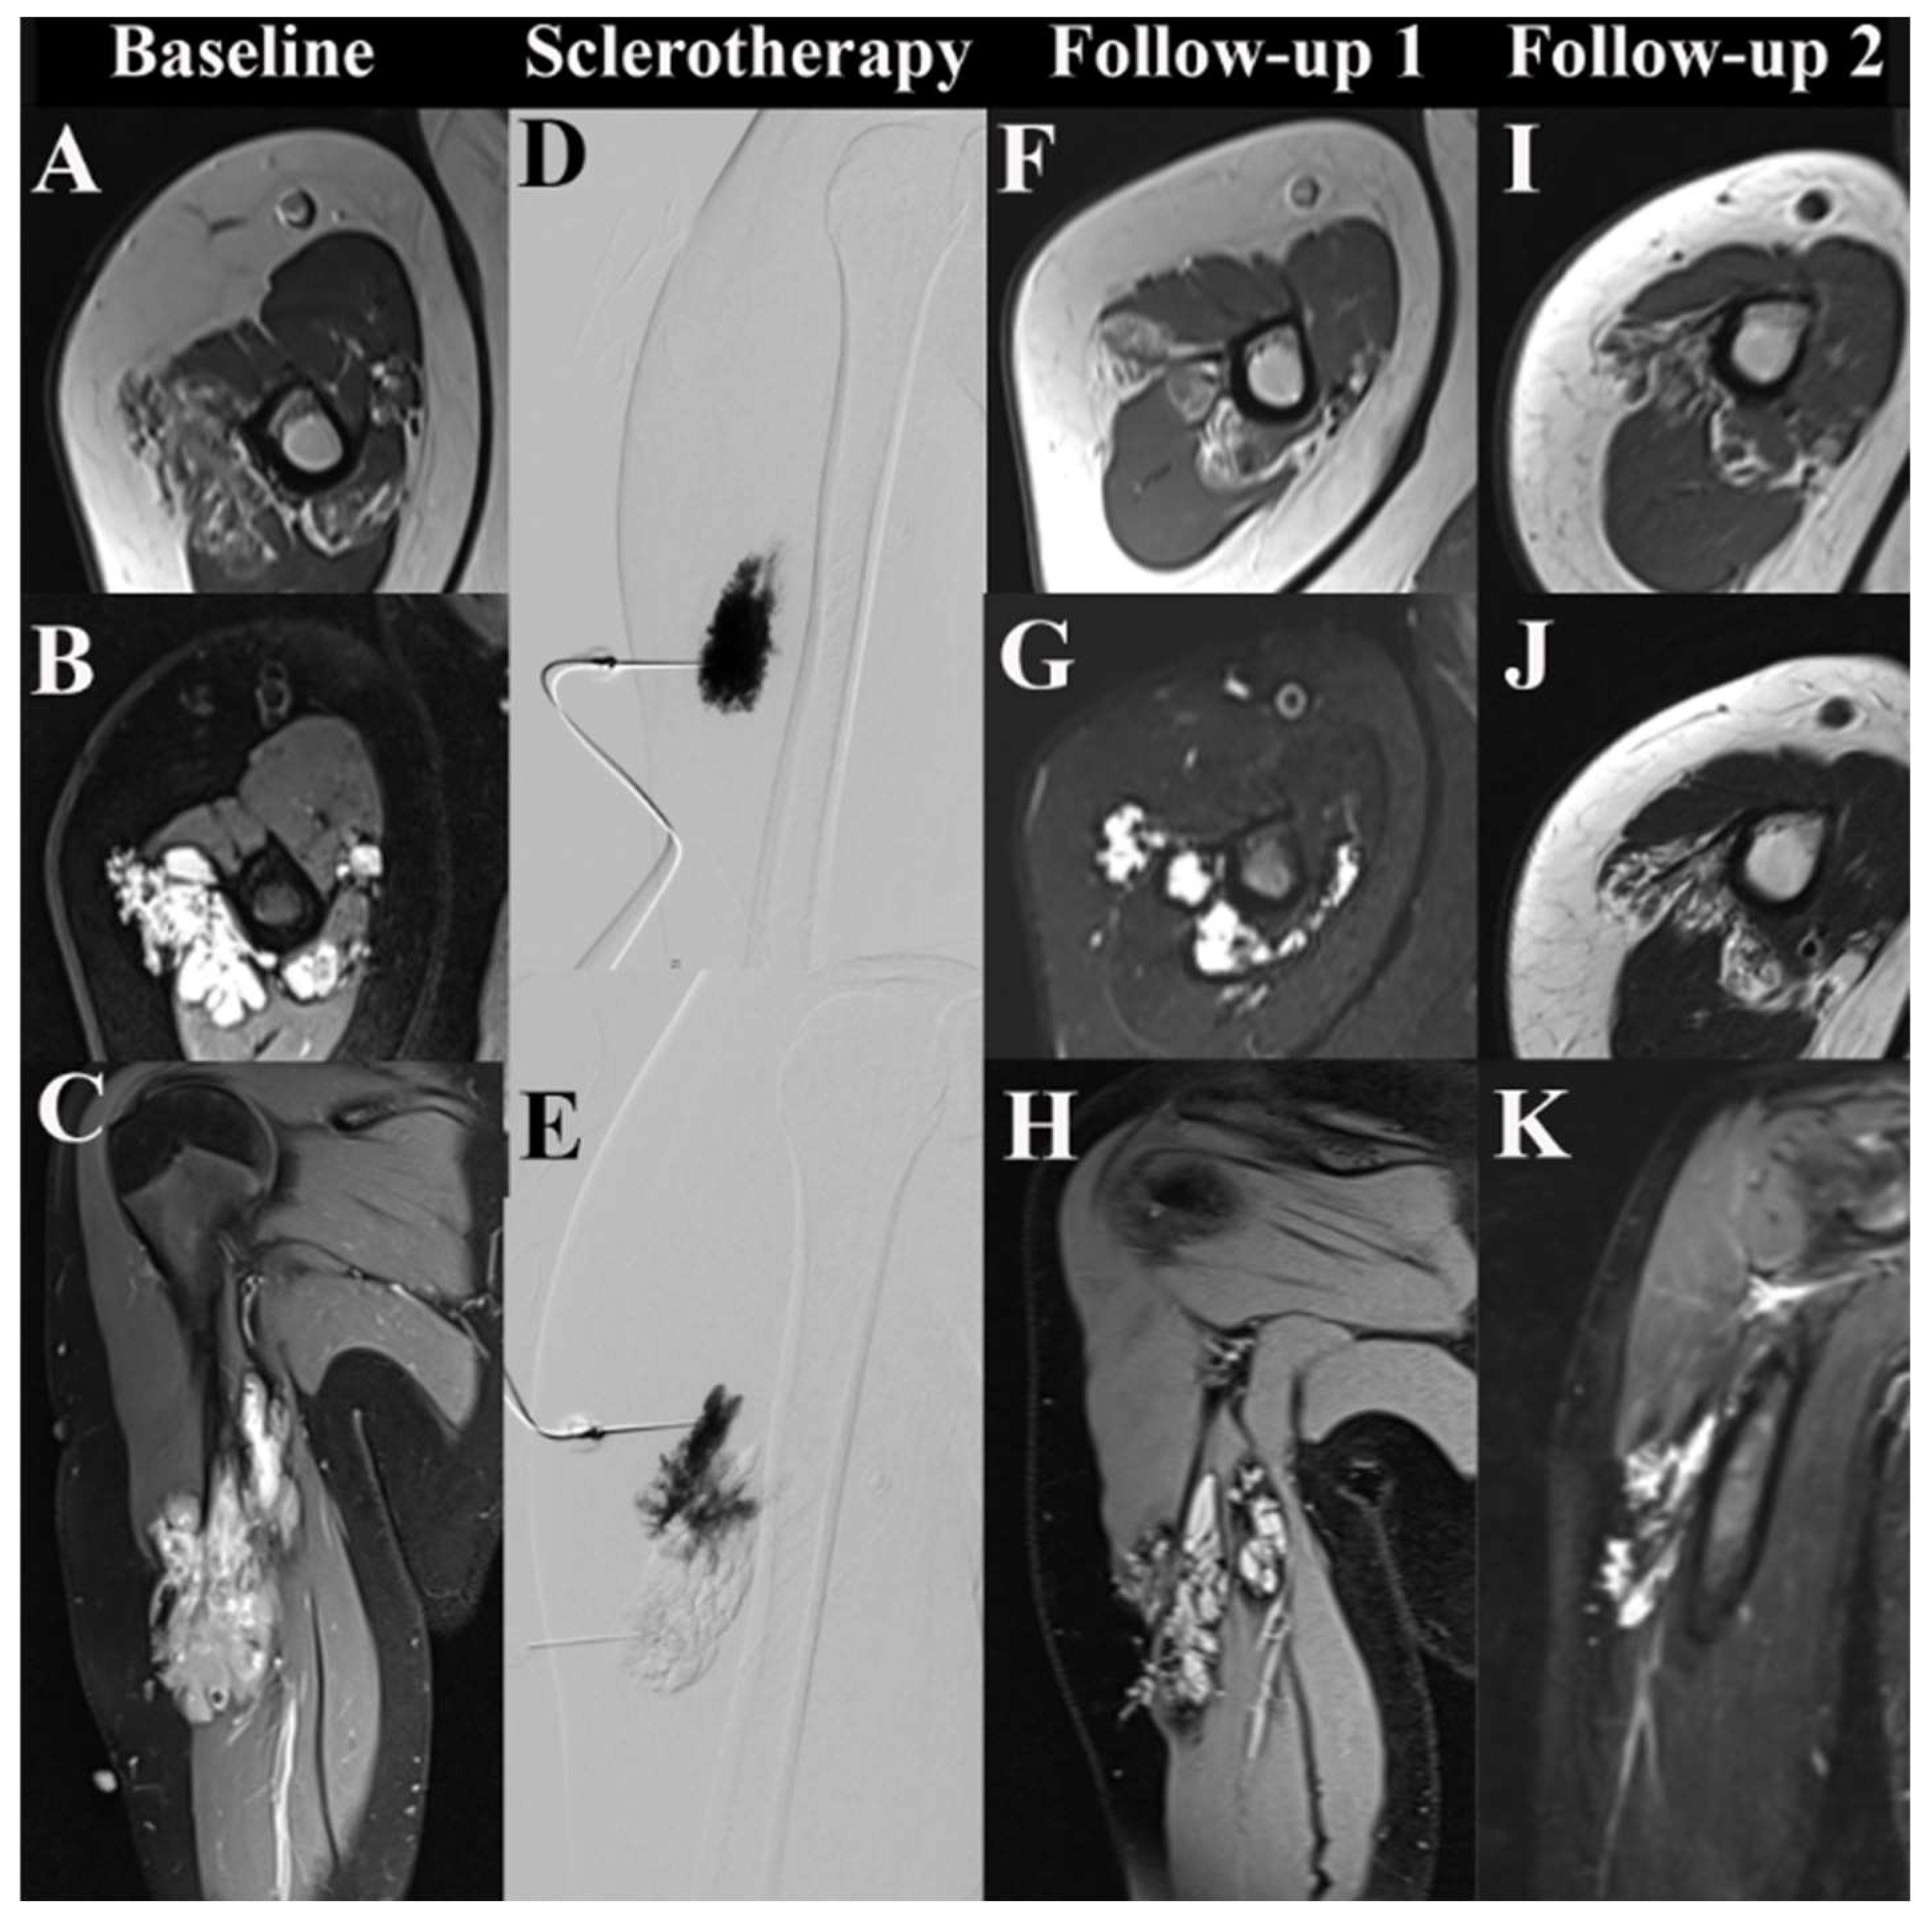

3.4. Imaging-Based Response Assessment

3.4.2. MSI Analysis